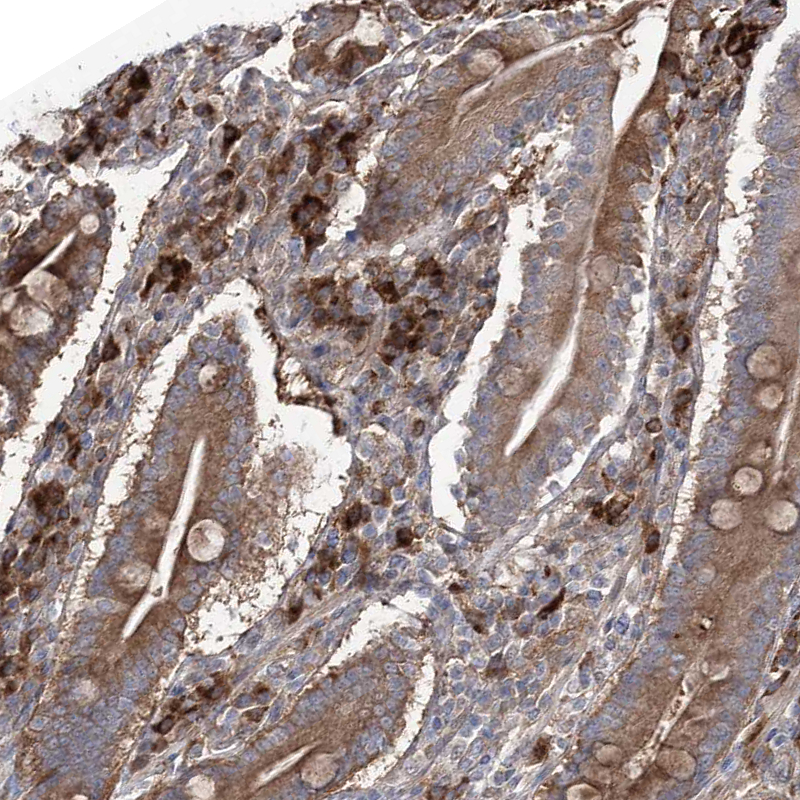

Immunohistochemical staining of human lung shows strong cytoplasmic positivity in macrophages.